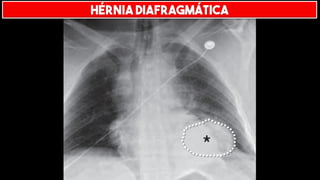

HÉRNIA DIAFRAGMÁTICA